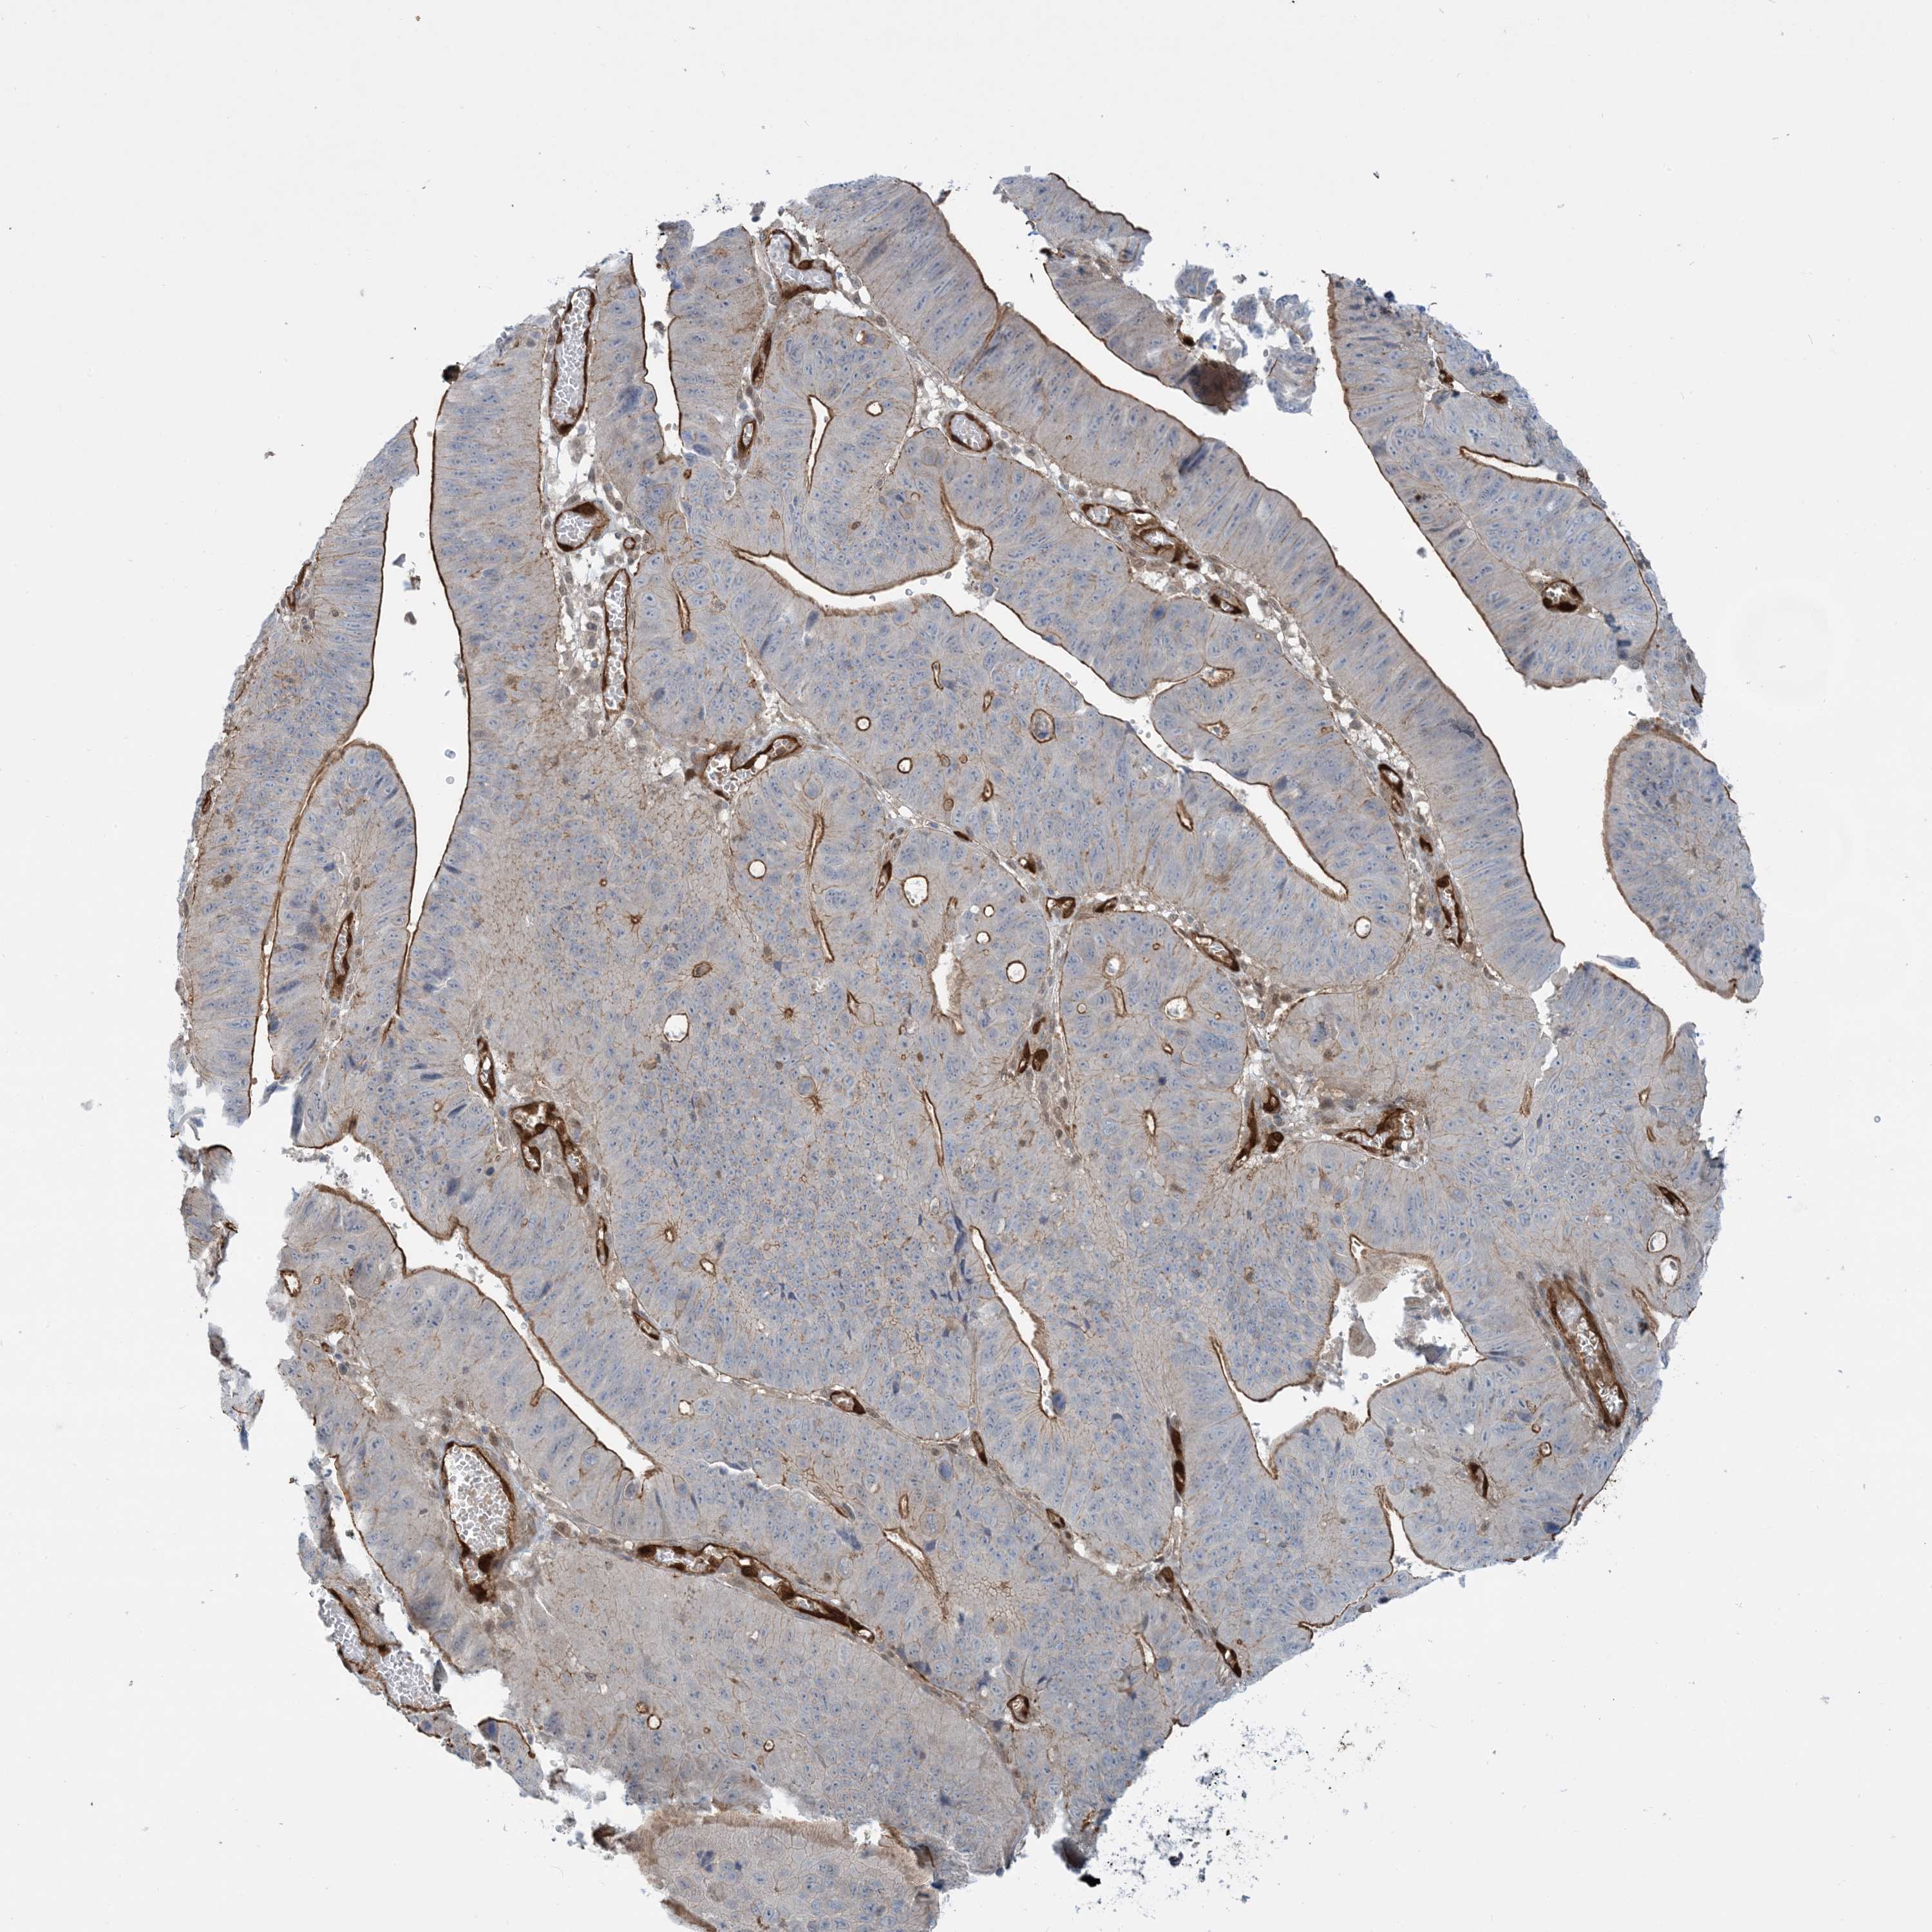

STOMACH CANCER - Protein expressioni

A mouse-over function shows sample information and annotation data. Click on an image to view it in a full screen mode. Samples can be filtered based on level of antibody staining by selecting one or several of the following categories: high, medium, low and not detected. The assay and annotation is described here.

Note that samples used for immunohistochemistry by the Human Protein Atlas do not correspond to samples in the TCGA dataset.

Antibody stainingi

Antibody staining in the annotated cell types in the current human tissue is reported as not detected, low, medium, or high, based on conventional immunohistochemistry profiling in selected tissues. This score is based on the combination of the staining intensity and fraction of stained cells.

Each image is clickable and will lead to virtual microscopy that enables deeper exploration of all samples and also displays staining intensity scores, fraction scores and subcellular localization as well as patient and tissue information for each sample.

Antibody HPA030989

Antibody HPA030990

Staining

High

Medium

Low

Not detected

Intensity

Strong

Moderate

Weak

Negative

Quantity

>75%

75%-25%

<25%

None

Location

Nuclear

Cytoplasmic/membranous

Cytoplasmic/membranous,nuclear

Adenocarcinoma, NOS